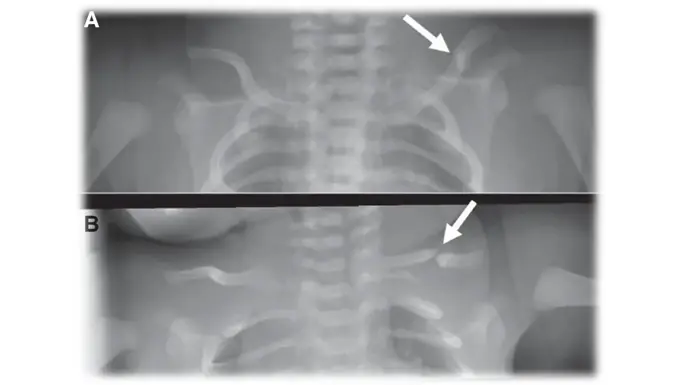

Doctors usually diagnose a newborn clavicle fracture through:

- Physical examination

- Imaging if needed (X-ray or ultrasound)

Sometimes, the fracture is only noticed later when a healing lump appears.

Healing and Recovery

- A small lump (callus) may form during healing and later disappear